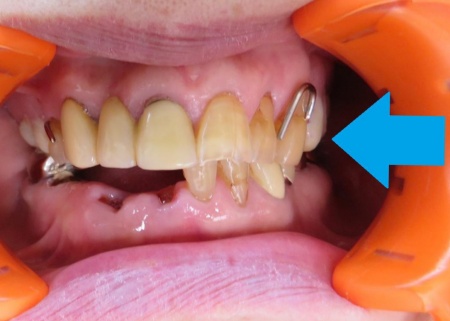

拝見したところ、左上前歯にかかっていた金属バネ(クラスプ)が折れており、入れ歯をしっかりと固定することができなくなっていました。

クラスプが折れたままでは、入れ歯の安定性が低下して外れやすくなる、残っている歯や歯茎に負担がかかる、食べ物を噛んだり会話をしたりすることが難しくなるなどのリスクがあります。

まず、現在の入れ歯と歯の位置関係を正確に再現するため、入れ歯を装着した状態で型取りを行います。